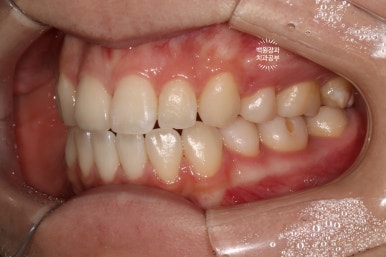

왼쪽: 우측 측면사진, 오른쪽: 좌측 측면사진

고개를 돌려 촬영한 사진을 보시면, 더욱 확실히 확인이 가능하실거에요.

우측 측면사진에 앞니가 하나 부족합니다. 정확히 얘기하면 대문니 - 중절치가 없죠.